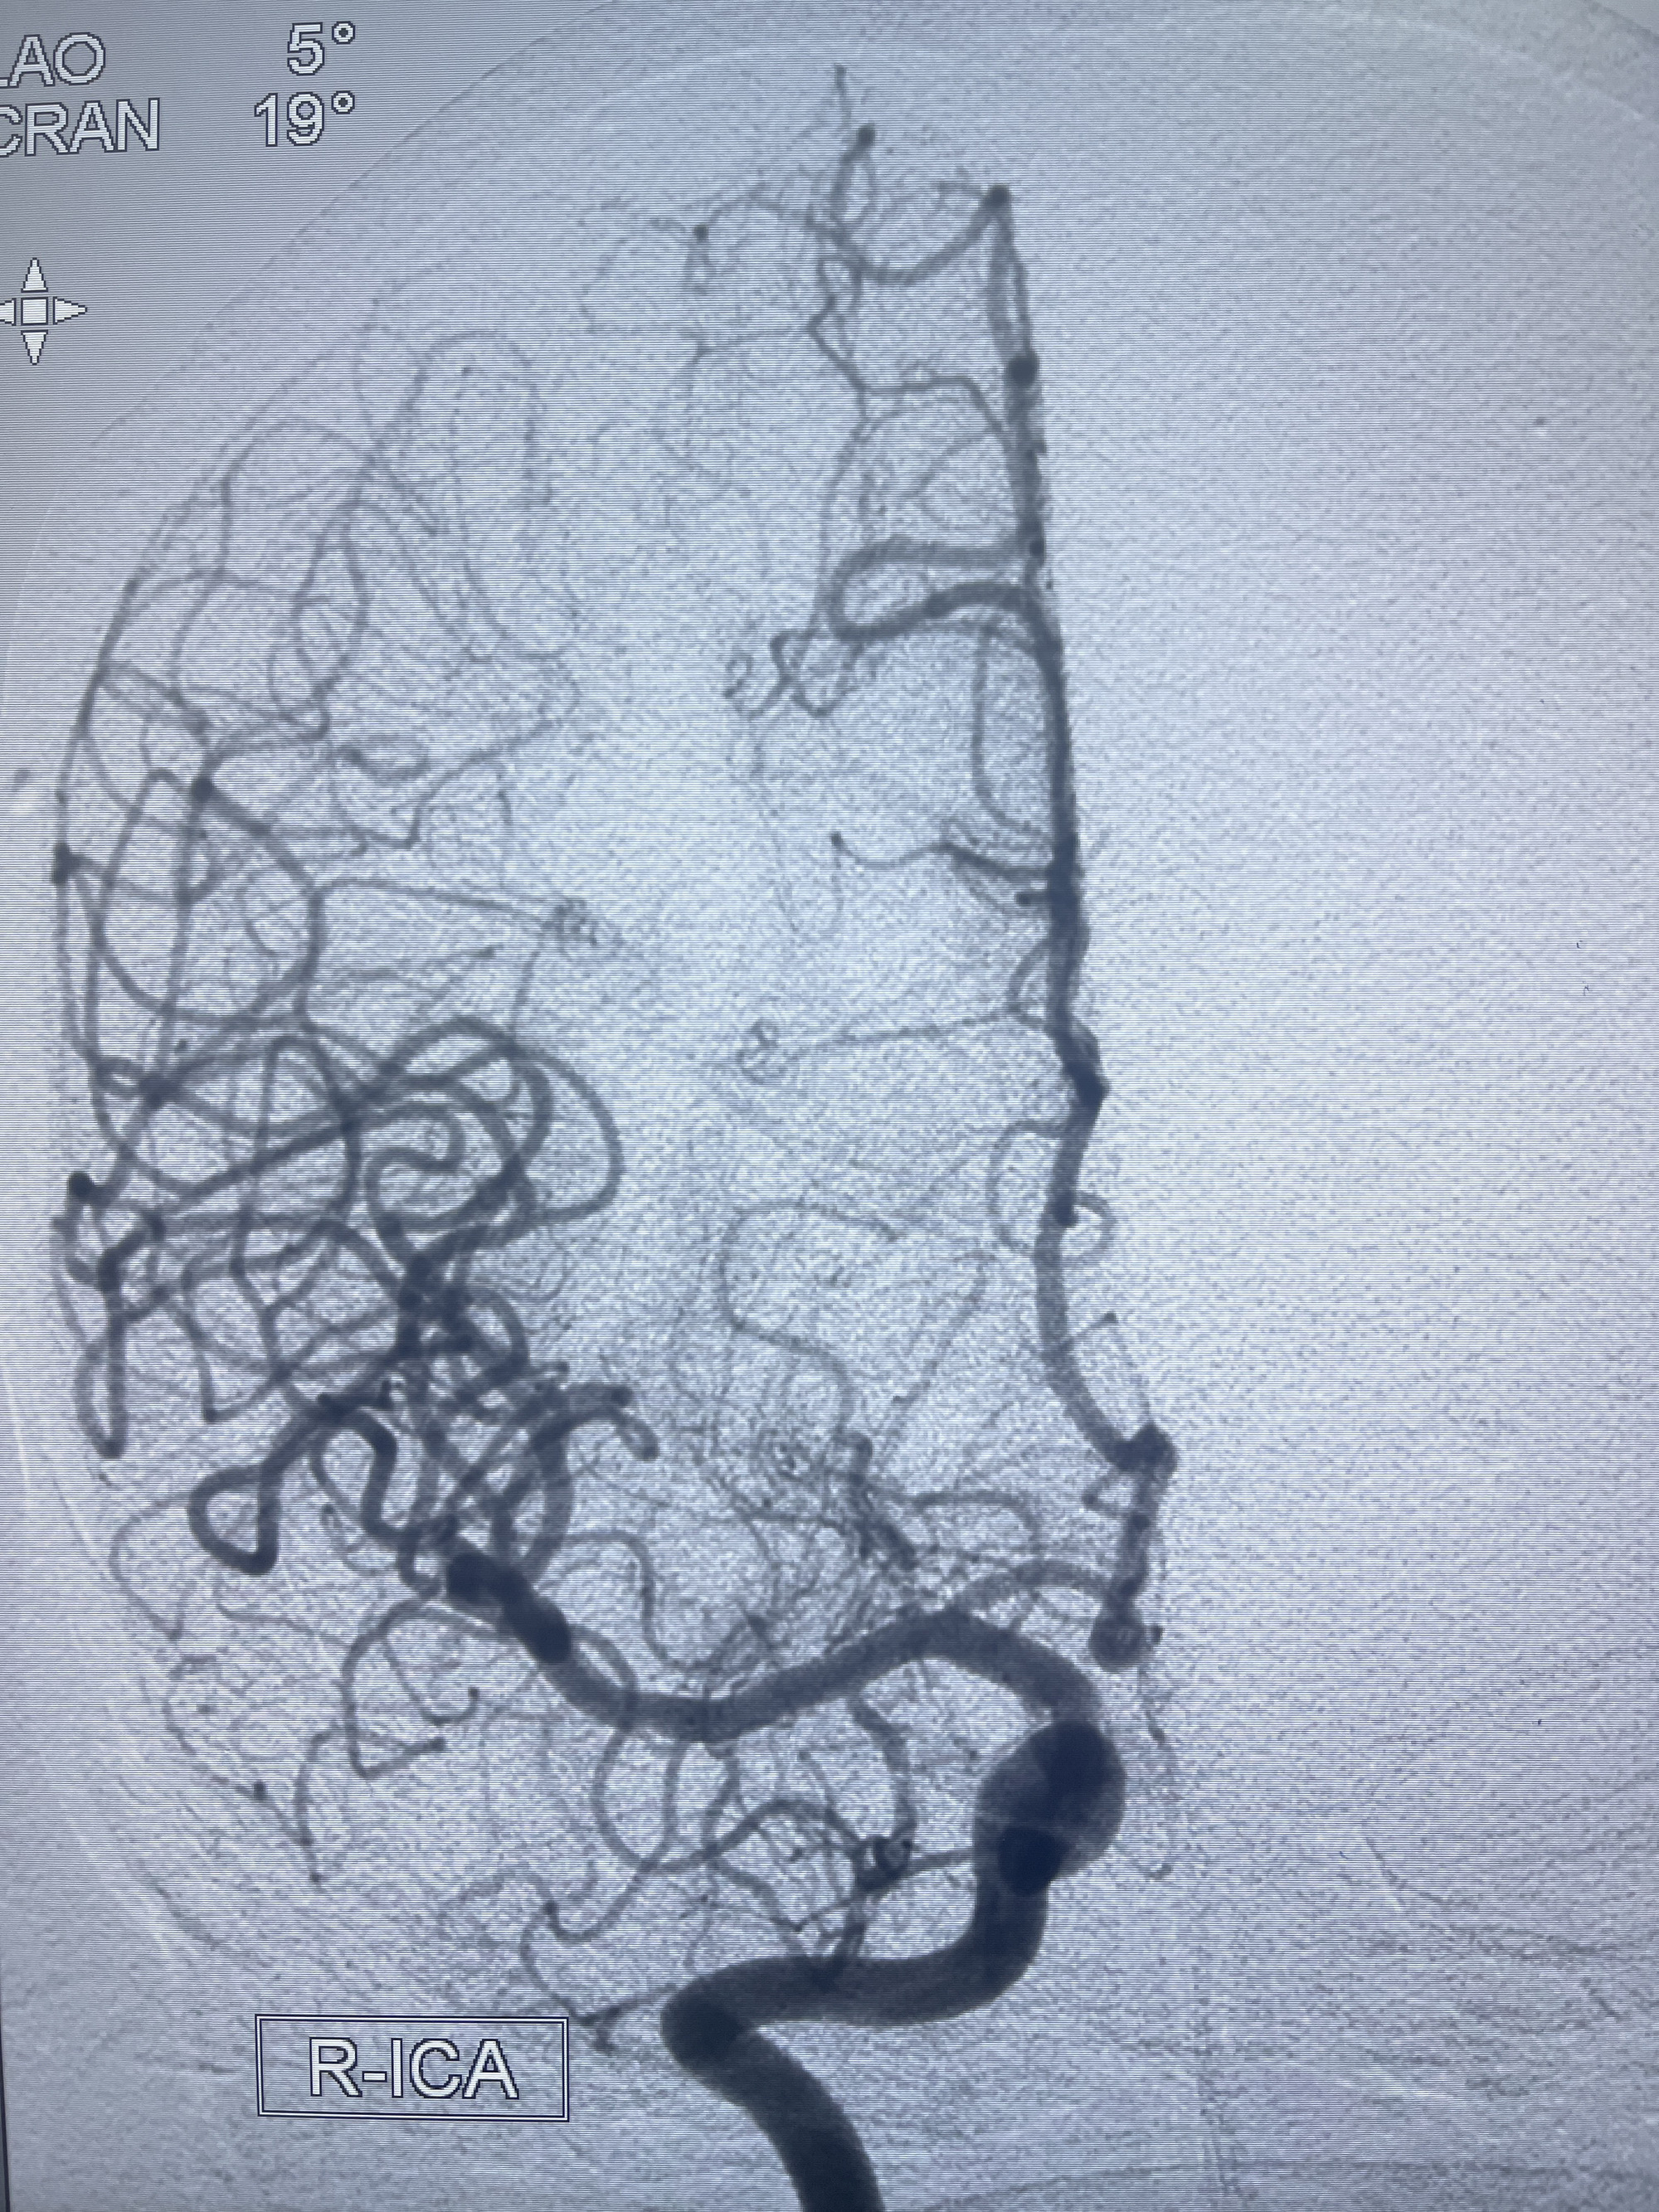

202.04.28脑血管造影:右侧大脑后动脉远段闭塞,右侧椎动脉V4段可见“囊状造影剂填充影”,大小7.64*7.65mm,可见PICA由动脉瘤发出;